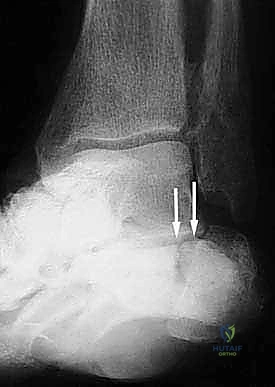

- الأشعة السينية (X-rays) متعددة الزوايا: لتقييم الانهيار العظمي وزوايا الكعب (مثل زاوية بوهلر وزاوية جيسان).

- الأشعة المقطعية ثلاثية الأبعاد (3D CT Scan): وهي الخطوة الذهبية والأهم في عيادة الدكتور هطيف. تتيح هذه الأشعة بناء نموذج ثلاثي الأبعاد دقيق للكعب المشوه، مما يسمح بتحديد أماكن الانحشار العظمي بدقة المليمتر، ومعرفة مدى تلف الأسطح المفصلية. بناءً على هذه الصور، يتم وضع خطة "القطع العظمي التصحيحي" قبل دخول غرفة العمليات.

- دمج المفصل تحت الكاحل (Subtalar Arthrodesis):

في الغالبية العظمى من حالات سوء الالتئام، يكون المفصل تحت الكاحل قد تدمر تماماً بسبب الخشونة والاحتكاك. الحل الجذري والنهائي للألم هنا هو "دمج" أو "تثبيت" هذا المفصل. يقوم الدكتور هطيف بتنظيف الغضاريف التالفة بالكامل، ووضع العظام في وضعها التشريحي الصحيح، ثم تثبيتها باستخدام براغي معدنية قوية جداً (Screws) لتلتحم وتصبح عظمة واحدة صلبة خالية من الألم.